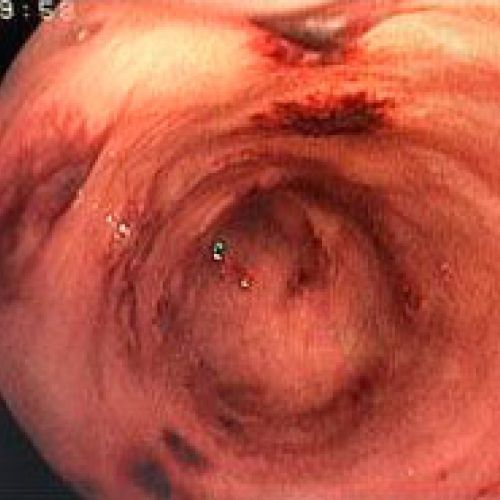

Endoscopia rígida y endoscopia flexible

En CiruVET realizamos procedimientos diagnósticos, como las endoscopias de última generación

En CiruVET contamos con el equipo necesario para los diferentes procedimientos diagnósticos y terapéuticos a nivel respiratorio y digestivo. En resumen, realizamos las siguientes pruebas diagnósticas: